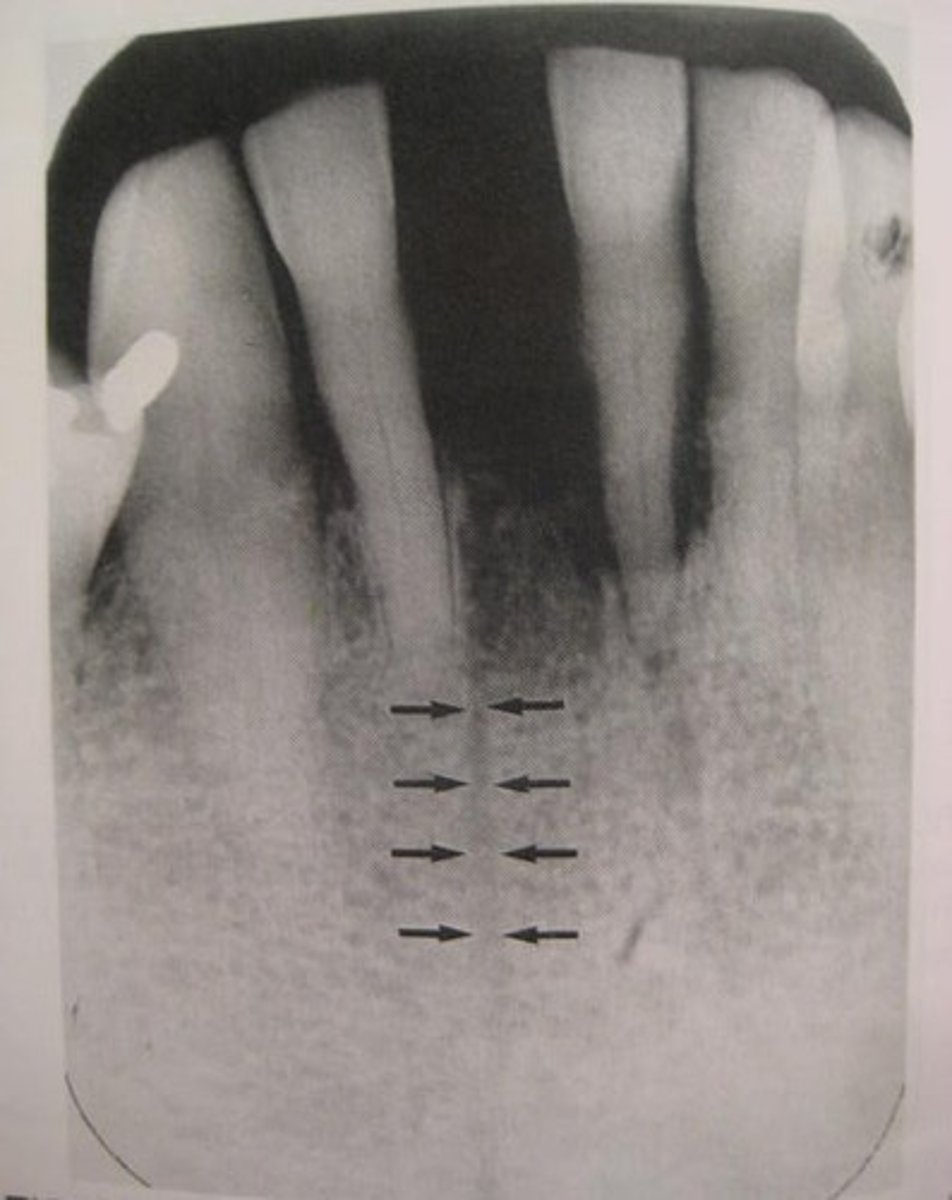

Nutrient canals

What is the radiolucent structure seen here?